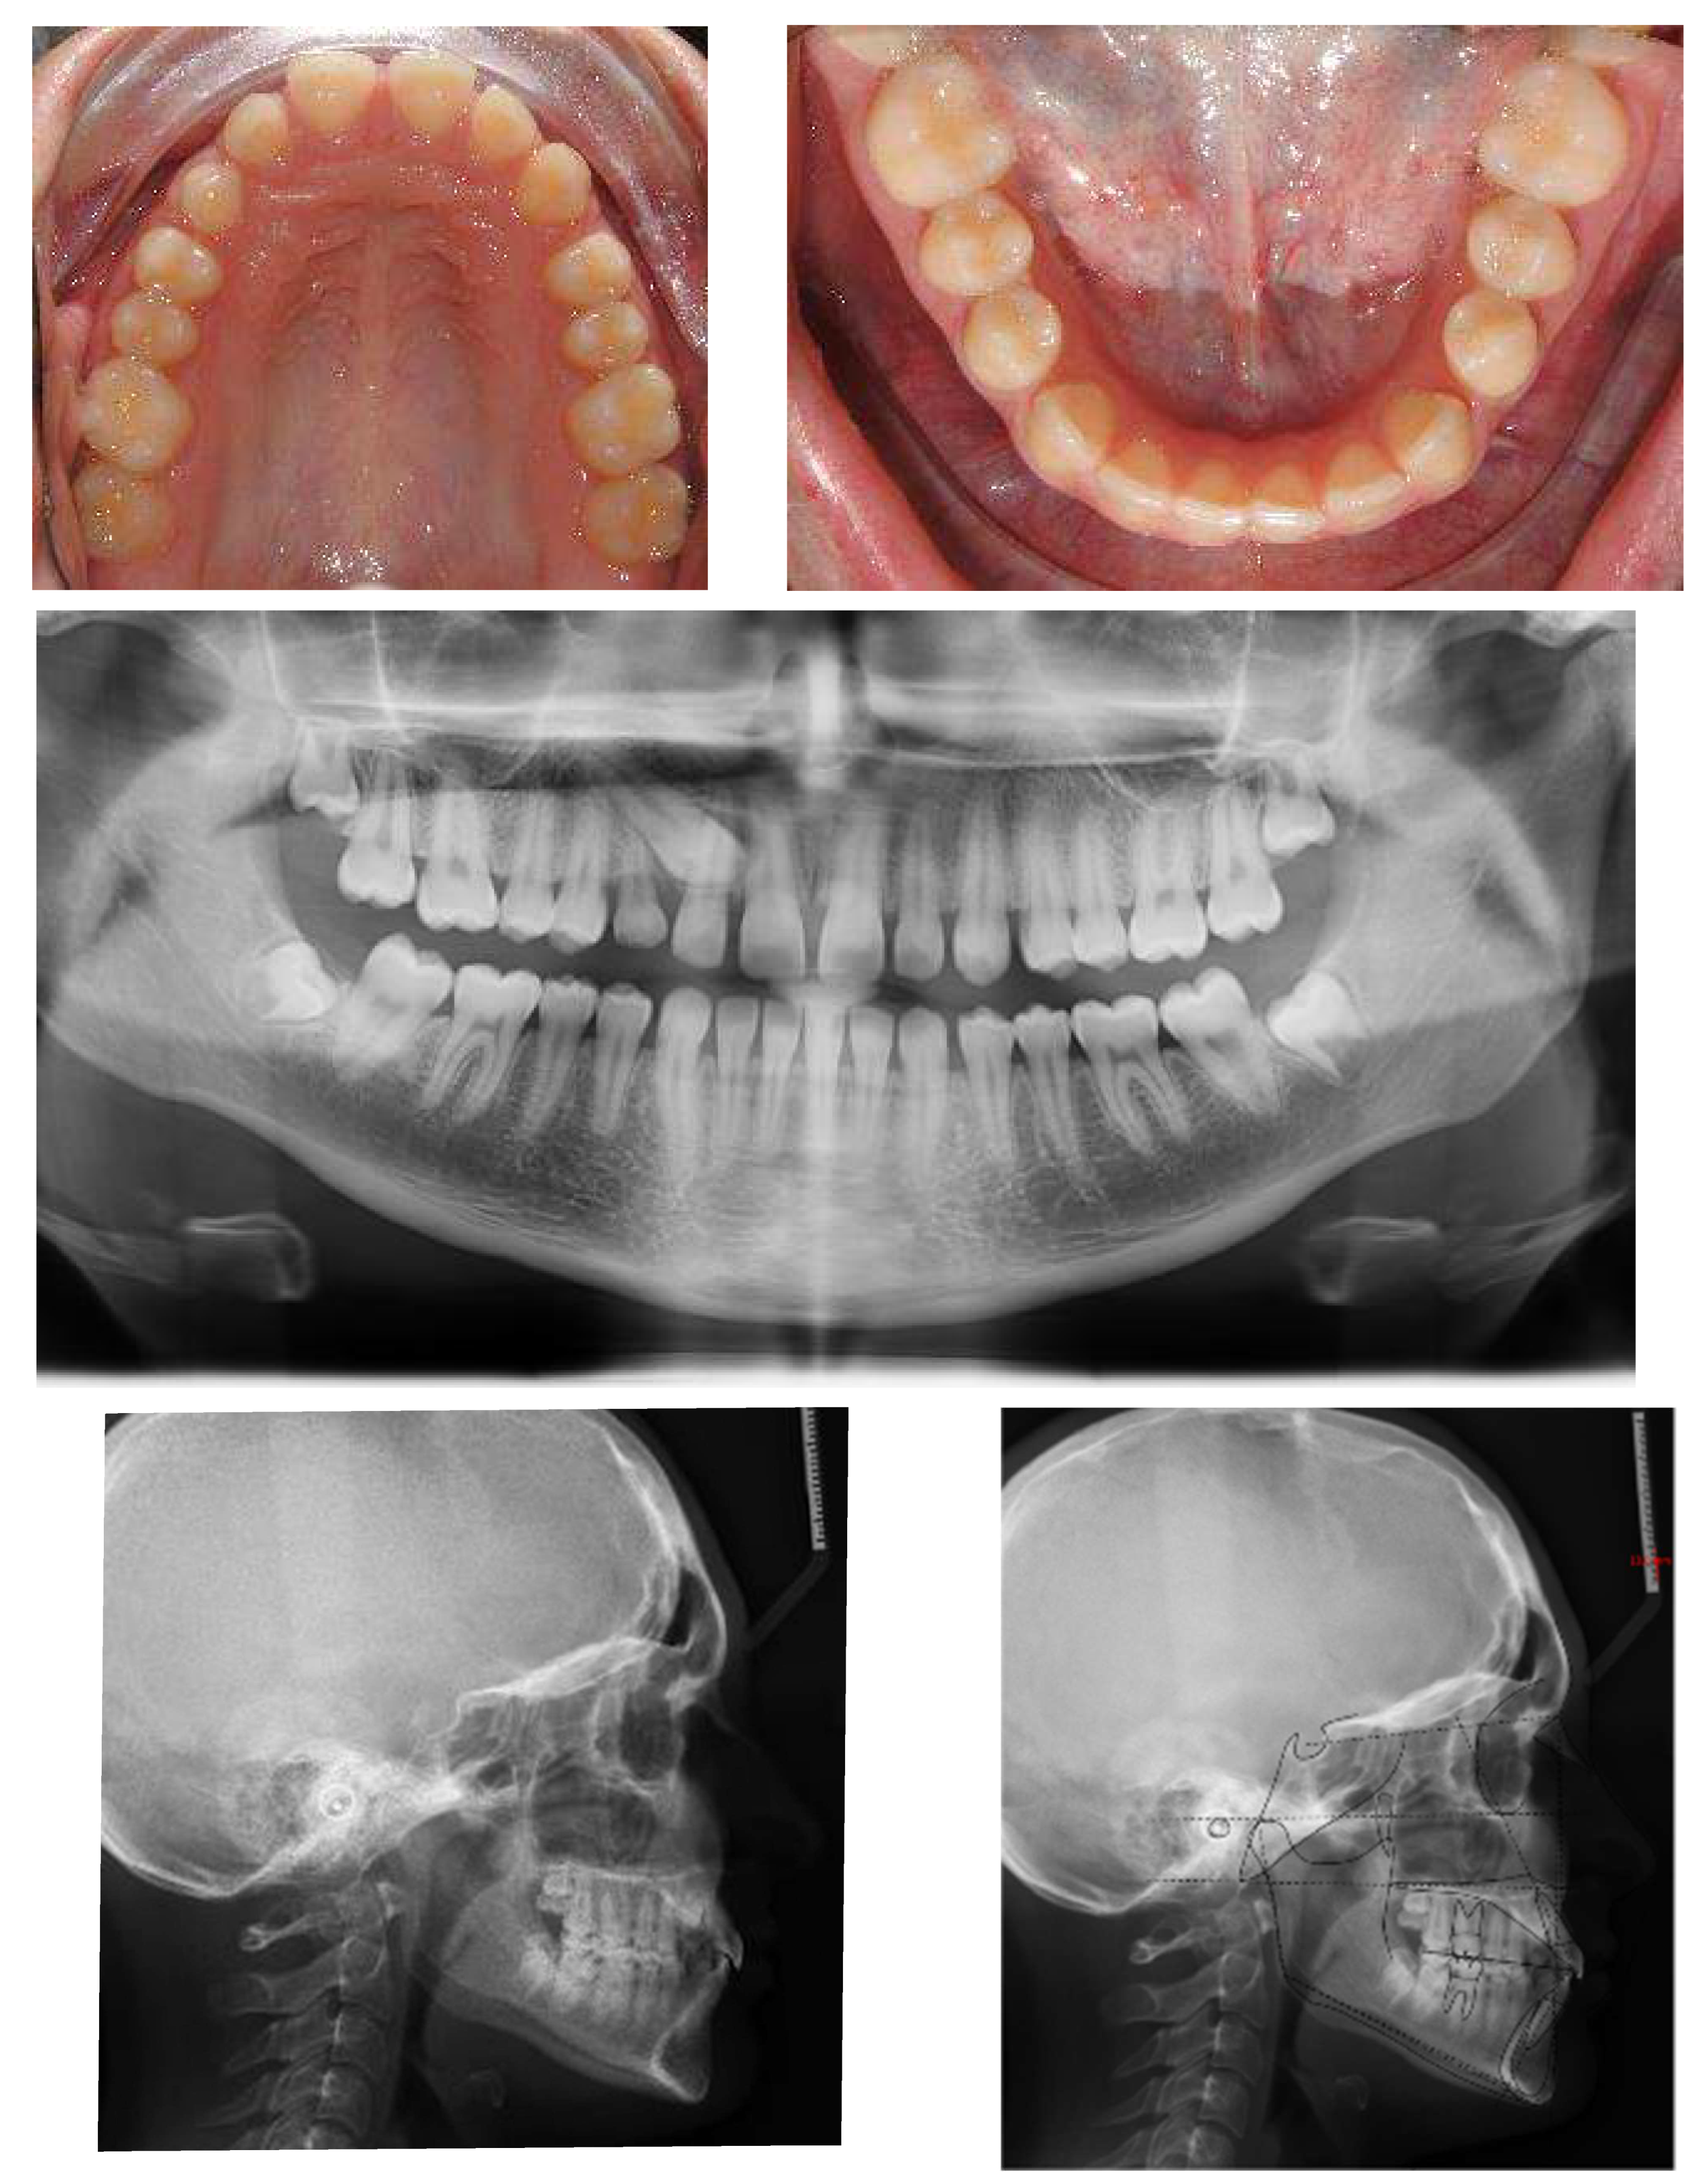

A 17-year-old female patient came for an observation in good general and oral health without any significant pathologies.

The chief complaint of the patient was the absence of a permanent maxillary canine. Her face, from a frontal view, appeared well-proportioned in the three-thirds with facial symmetry.

From a lateral view, the profile appeared straight and a normal nasolabial angle, labiomental sulcus, and lip competence was represented. The initial records were collected and X-rays were taken (Figure 1).

A 17-year-old female with dentoskeletal Class I with an impacted upper right canine before treatment.

Intraorally, the patient had Class I molar and canine relation on both sides, along with normal overbite, overjet, and the retention of the deciduous canine.

The cephalometric analysis showed a skeletal Class I (ANPg +1.7°) with a good proportion of the maxillaries (SNA 84°; SNB 82.3°) in a normo-divergent vertical pattern (SN^Go-Gn = 32.8°) and a good inclination of the upper and lower teeth, respectively (I/ANS-PNS 116.2°; i/GoGn 91.6°) (Table 1).

The panoramic X-ray showed unilateral permanent canine displacement in sector four with an alpha angle of more than 53° degrees according to the Ericson and Kurol classification (Figure 2).

Pre-treatment panoramic X-ray with the evaluation of alpha angle and sector according to the Ericson and Kurol classification.